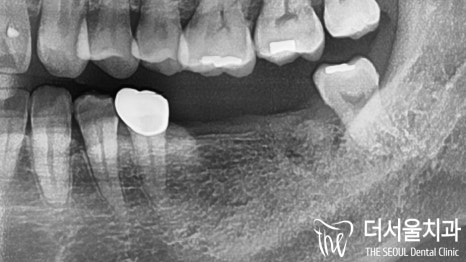

뿌리만 남아있는 곳은 물론이며

이미 빠져버린 곳을 볼 수 있는데요.

임플란트가 하루 빨리 필요한 것으로

판단이 들었습니다.